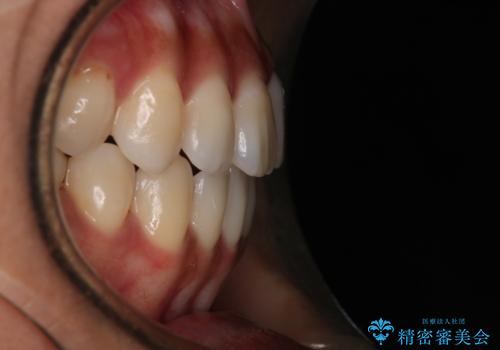

- 開咬を主訴に来院されました。前歯部に開咬、右側大臼歯部にクロスバイトが認められます。ワイヤー矯正の審美装置で治療し、ゴム掛けを行いながら噛み合わせを改善しました。

主訴である開咬と右側大臼歯部クロスバイトを改善でき、しっかりと噛むことができるようになりました。